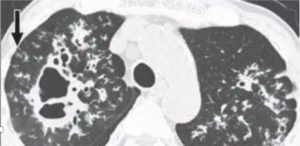

The characteristic radiographic and high-resolution CT findings consist of innumerable, 1- to 3-mm diameter nodules randomly distributed throughout both lungs